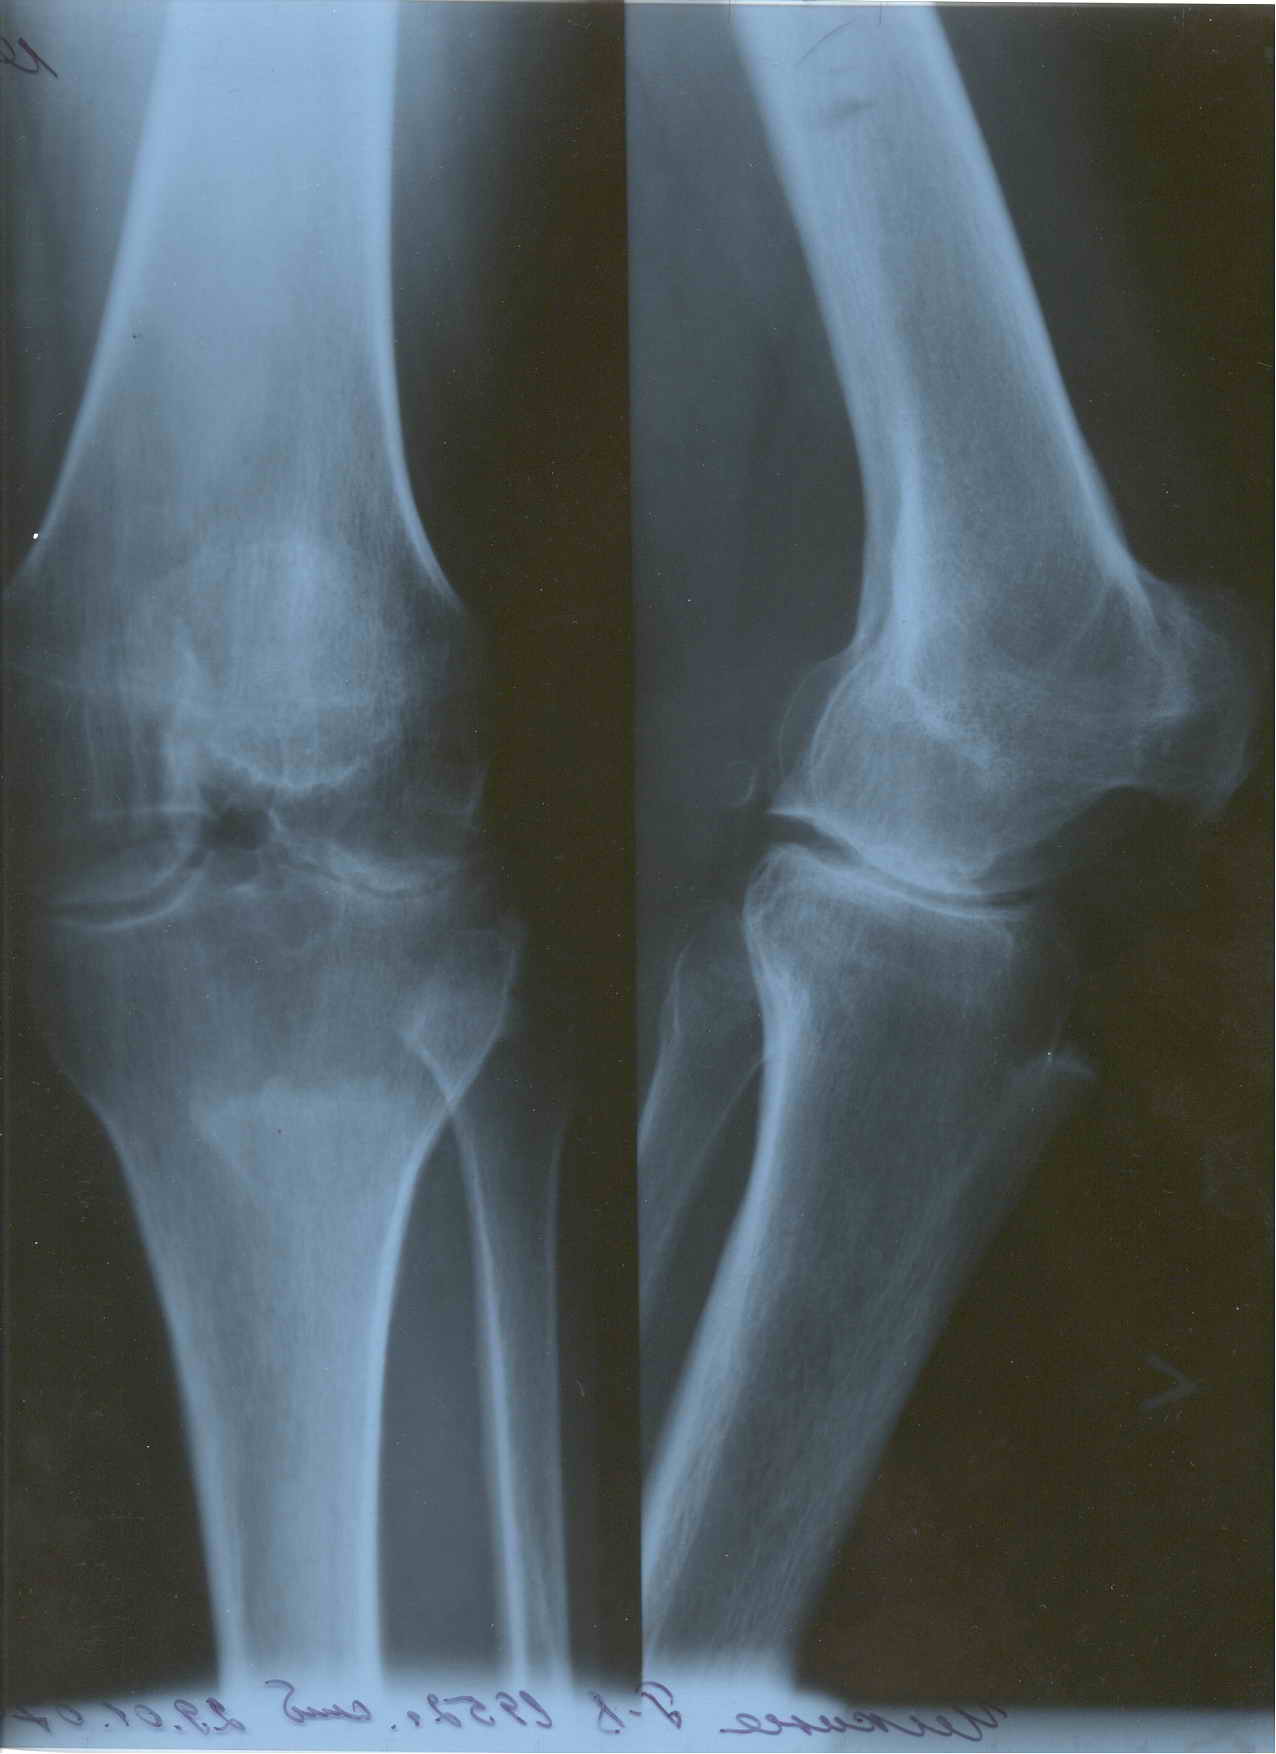

Коллеги занимающиеся TKR прошу совет. Обратилась пациентка 55 лет без сопутствующих проблем со здоровьем для установки коленного сустава по линии ФСС (показания установлены комиссией год назад). В программе эндопротез Зиммер LPS Legacy. После осмотра пациентки возникли сомнения в целесообразности артропластики. История: в 1998 году после серии кеналогов перенесла септический гнойный гонит с исходом в фиброзный анкилоз коленного сустава в позиции сгибания 40 град и костный анкилоз надколенниково бедренного сустава. В 1999 году в ЦИТО рекомендовано эндопротезирование (в тот период еще были движения). С 2000 года подвижности нет. Соответствующая гипотрофия 4-гл. мышцы бедра, относительное укорочение и т.д. Вопросы? 1. Целесообразно ли эндопротезирование вообще? 2. Реально ли использование вышеуказанной модели эндопротеза в данной ситуации или следует установить "Хинч"? 3. Чем бы Вы помогли пациентке, если не надо протезировать ( коррегирующий артродез приходит на ум)? Социально - инвалид 3 группы, пенсионер по возрасту, не очень богата. Спасибо заранее. Доктор А Рыков. Хабаровск. Снимки в прищепке.

Имя     : Снимок 1.jpg